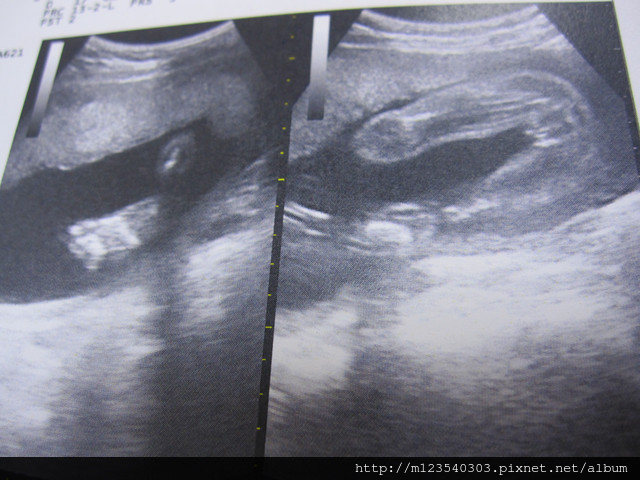

此外~還是要來看看小寶貝的狀況

這是握拳頭的小手手

一邊是小腳腳

另一邊就可以看得出性別了~是妹妹喔!!

醫生說:小寶貝的狀況不錯大小也剛剛好....所以...都胖在媽媽身上ㄟ....